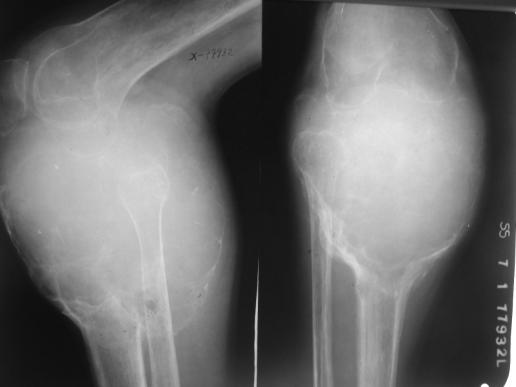

骨肉瘤:最常见的恶性骨肿瘤

临床:1、年龄:青少年(11-20岁占50%),男多于女;2、部位:以膝关节、肱骨上端多见。;;发生于干骺端。

影像学表现:1.源于骨髓腔的不规则的骨破坏和骨增生;2.骨皮质破坏,骨膜增生–葱皮样、放射状,Codman三角(袖口征)-骨膜增生被破坏形成

3.软组织肿块,其内见肿瘤骨(诊断骨肉瘤要点)。云絮状、针状、放射状、斑块状

桡骨上段成骨型骨肉瘤:骨质增生硬化,并有骨膜反应,软组织肿块

股骨下端溶骨型骨肉瘤